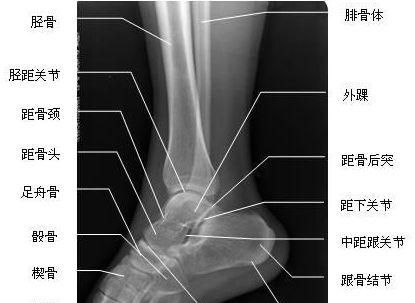

1、X线检查:在X线检查上,我们可以看到所有的骨性结构,包括胫骨、腓骨、距骨以及他们所组成的踝关节。无论是外踝横行骨折或者是内踝垂直骨折,在X线上都可以被发现。也就是说,为了确诊,伤后我们首先需要做的就是做一个X线,排除骨性结构的损伤。